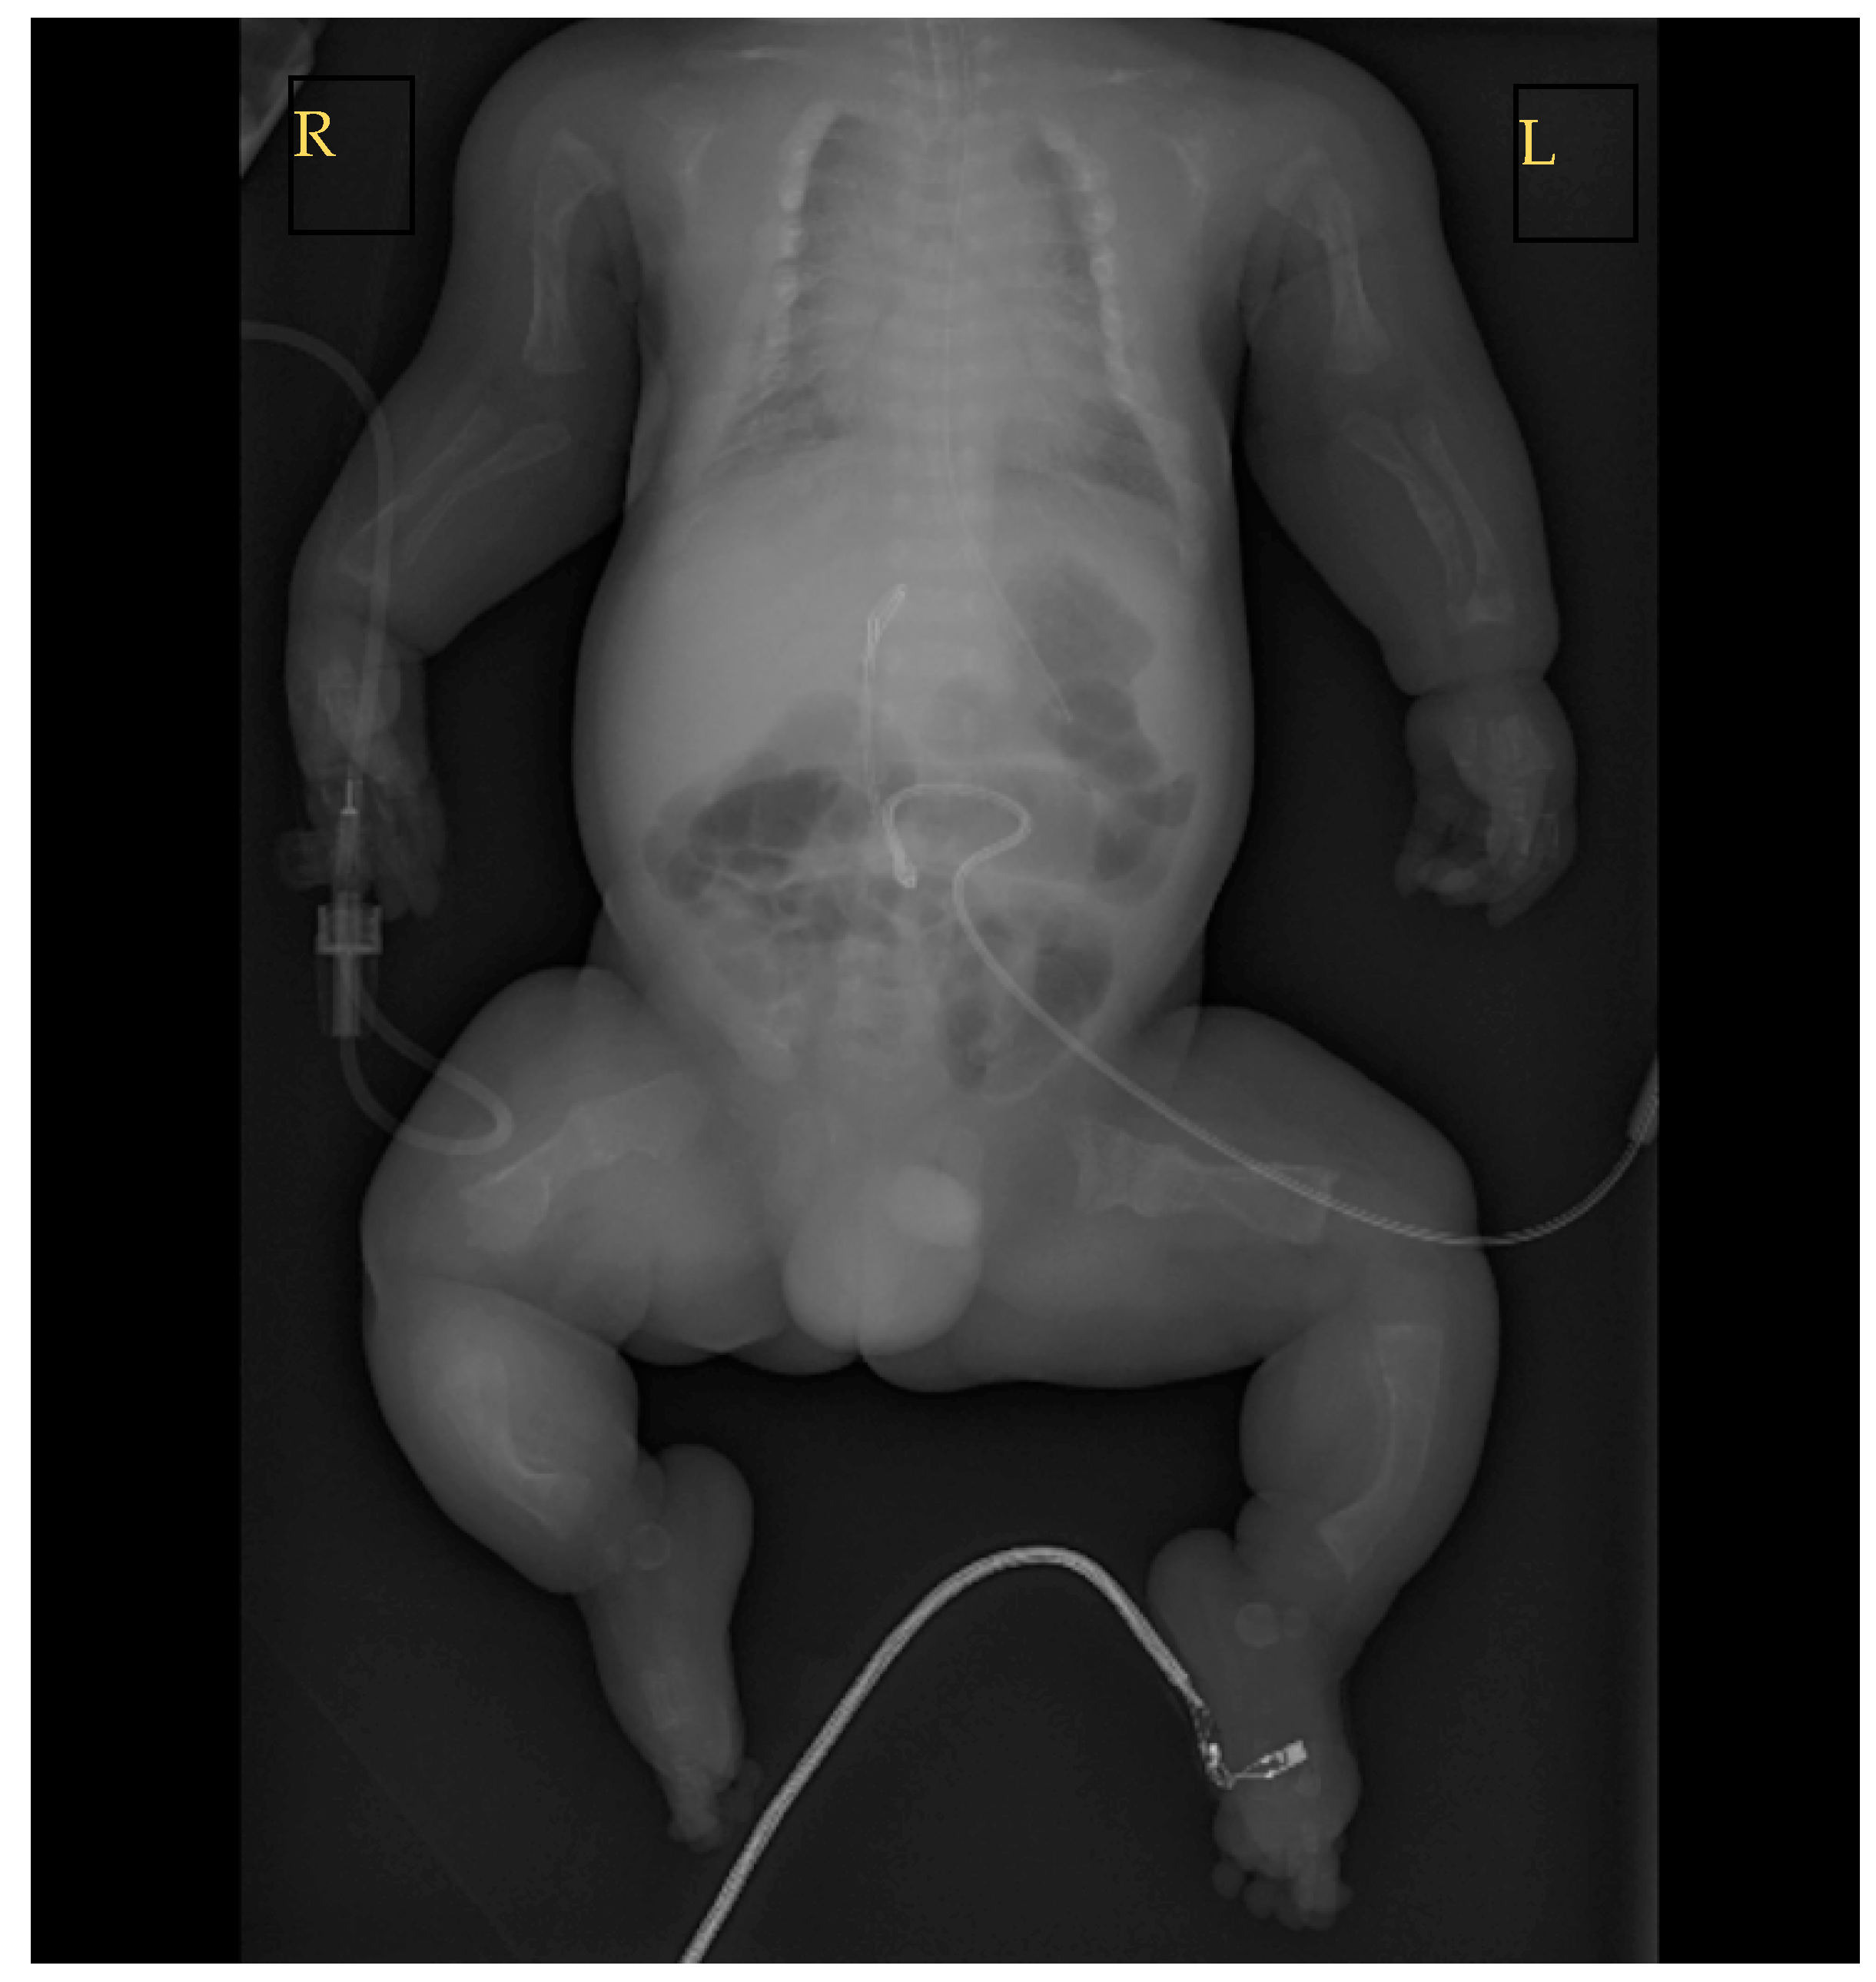

2.2. Birth and Early Treatment

2.3. Further Patient Investigations, Management, and Treatment after Birth

| Whole body | Disproportionate |

| Skull | Uneven contour; mobile skull vault; fragmented skull bones; wide spaces between cranial sutures; wide anterior fontanel |

| Ears | Very low-set |

| Neck | Short |

| Intermammillary distance | Wide |

| Umbilicus | Low-set |

| Long bones | Very short humerus and femurs |

| Hands | Swollen |

| Feet | Clubfoot |